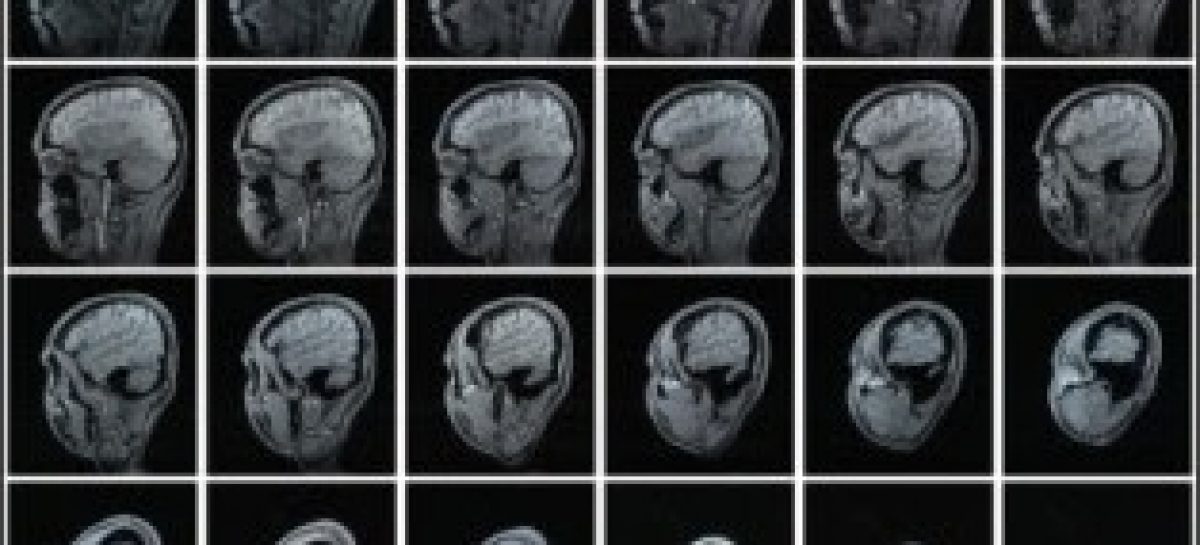

Em um dos experimentos, foi comparado um grupo de camundongos sadios e outro geneticamente modificado para desenvolver um quadro semelhante ao Alzheimer. Nesse modelo, para induzir a formação das placas beta-amiloidais no cérebro dos animais, é inserido no genoma do roedor uma mutação dupla na proteína APP (proteína precursora amiloidal), que dá origem ao peptídeo beta-amiloide.

Os fragmentos radiomarcados foram injetados nos dois grupos de animais e, após diferentes tempos, os pesquisadores faziam a contagem de radiação em cada um dos órgãos, com auxílio de um contador de radiação gama.

“Dependendo do fragmento, observamos que entre 3% e 5% das moléculas radiomarcadas conseguiram de fato chegar até o cérebro dos animais geneticamente modificados, o que é considerado um índice satisfatório. Atualmente, há radiofármacos usados em outros tipos de diagnósticos nos quais a porcentagem de especificidade fica em torno de 1%”, contou Malavolta.

Nos animais controle (sadios), segundo a pesquisadora, as atividades radioativas referentes aos peptídeos radiomarcados ficaram ao redor de 0.5% no cérebro.

Nos testes in vitro, o índice de interação dos fragmentos radiomarcados com as células cerebrais dos camundongos com Alzheimer foi de 50%. Já com as células dos camundongos sadios o índice ficou entre 10% e 12%.